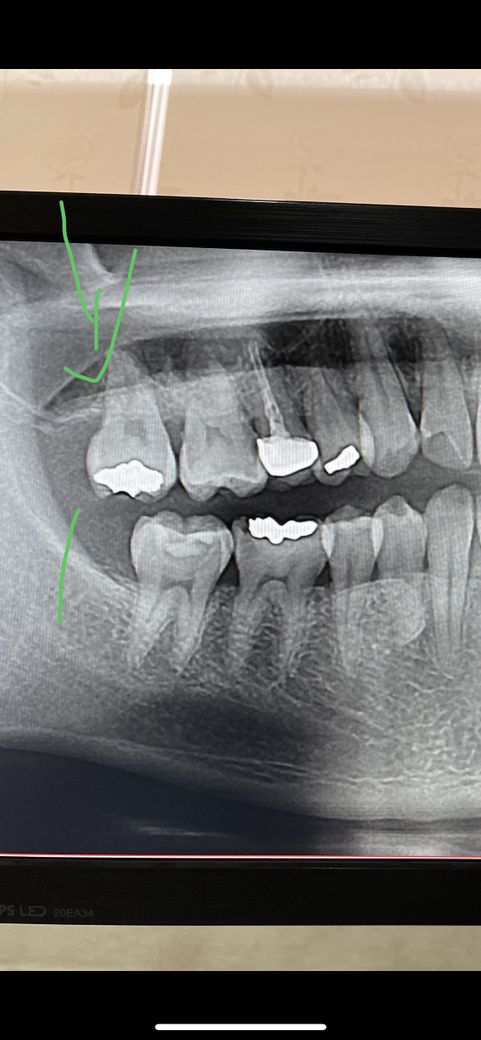

오른쪽 위 맨끝 어금니 치아가 한번식 욱신 하이 아픕니다..

딱딱한거 씹으면 욱신하이 아픕니다

가만히 잇어도 가끔 욱신하이 아픕니다

치아를 두들겻을댄 아프지 않으며

시린거에도 반응은없습니다

잇몸을 쑤시니 아픕니다…

충치도 아니고 왜아픈거죠??..

단순히 파노라마 엑스레이만으로는 정확한 답변이 어렵습니다.

구강내 검진과 필요시 스탠다드 엑스레이 촬영을 통해 정확한 진단을 받으셔야 치료계획 수립이 가능합니다.

직접 검사를 해봐야 알 수 있을것이지만, 사진만봐서는 특별히 문제는 없어보입니다.

앞쪽 잇몸이 안좋아보이긴 하지만 사진상으로 불명확하여 직접 검사를 해봐야 합니다.

사진만으로는 정확히 어떤 상태인지는 알 수 없습니다. 다만 인레이 보철물이 상당히 큰 것으로 보아 치아에 금이 갔을 가능성도 있어 보입니다. 만약에 금이 갔다고 생각하면 현재 질문자님이 느끼는 통증의 대부분이 나타날 수 있기 때문입니다. 하지만 이를 평가하기 위해서는 인레이 보철물을 제거해보아야 하는데 제거 이후에도 증상이 가라앉지 않는다면 발치를 해야할 수도 있기 때문에 불편감이 크지 않다면 조금 더 지켜보는 것도 방법입니다.